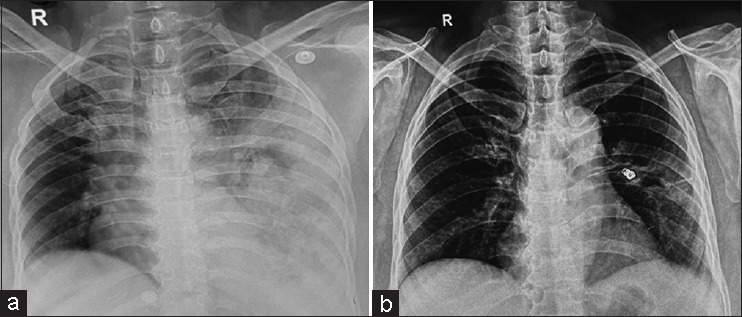

Necrotizing pneumonia causing left descending pulmonary artery pseudoaneurysm: A rare entity.

坏死性肺炎引起左降肺动脉假性动脉瘤:罕见病例。